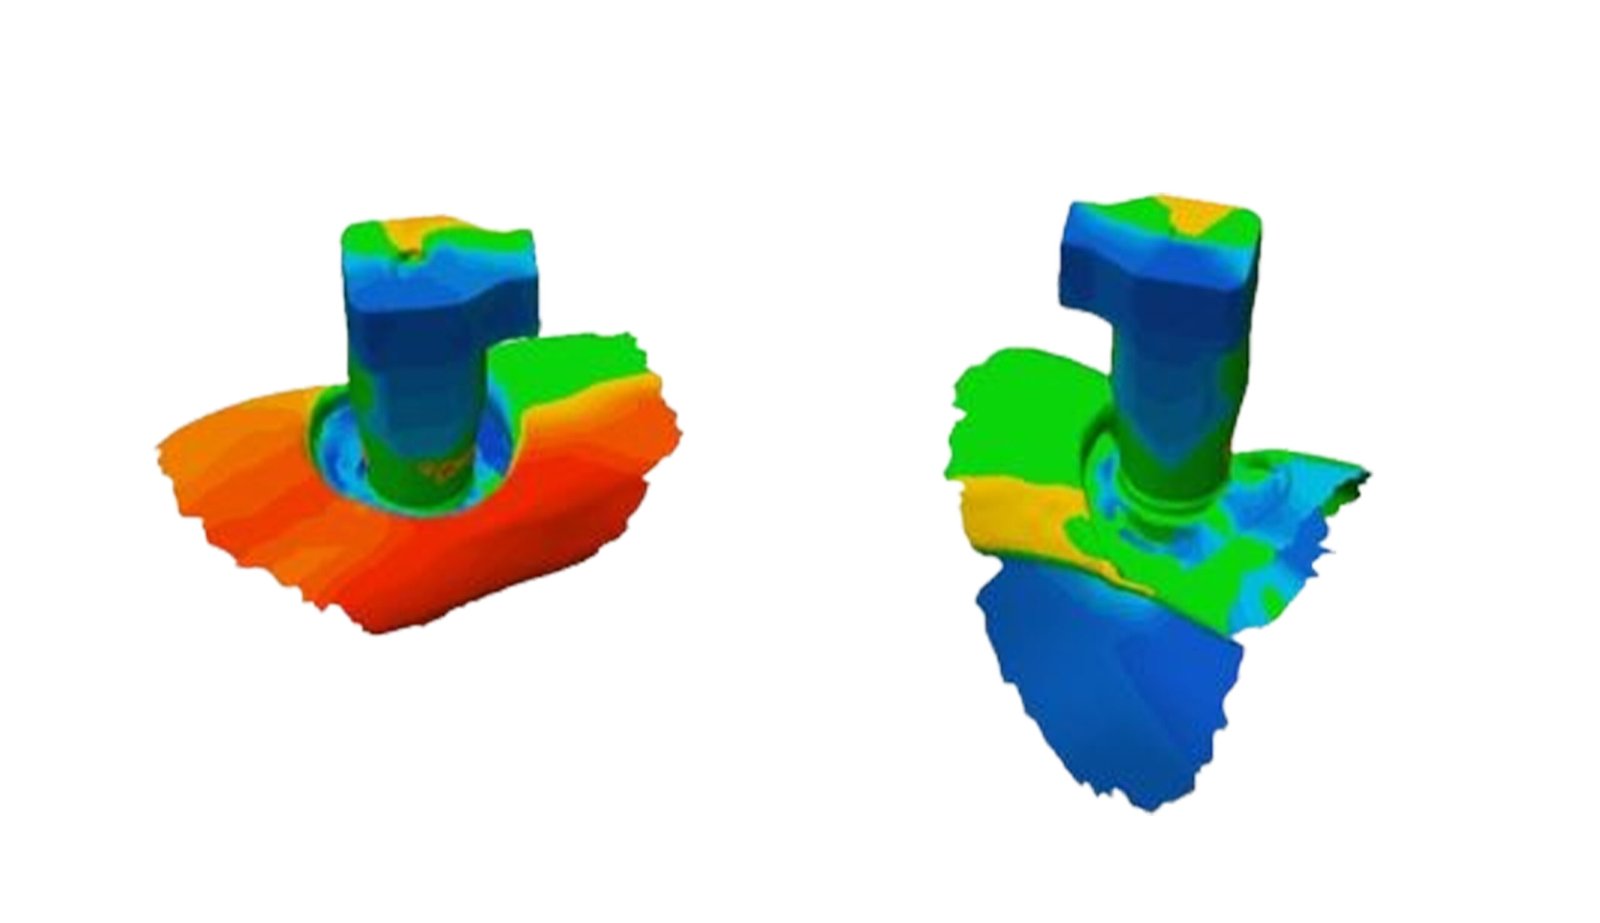

This section specializes in high-precision 3D deviation mapping to compare pre- and post-treatment anatomical or implant-related geometries. Using advanced superimposition and deviation algorithms, we quantify micro-level shifts, deformation zones, and structural discrepancies with sub-millimeter accuracy. These analyses support quality control, surgical verification, and design validation. The resulting deviation heat-maps provide clear, data-driven insights that enhance clinical decision-making and device optimization.